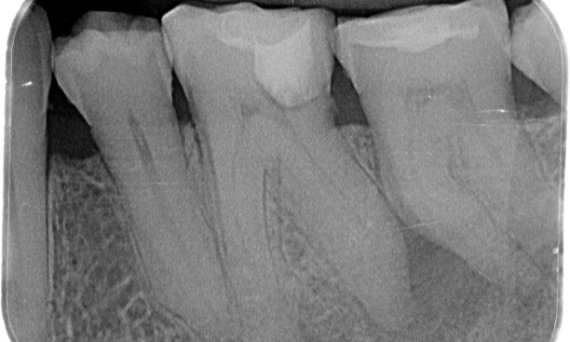

Avant : Radiotransparence périapicale associée principalement à la racine distale et à la perte de la lamina dura sur la racine mésiale.

Après : TruNatomy a été choisi dans ce cas pour permettre une approche adaptée aux caries et une préservation de la dentine péricervicale, en particulier au niveau de l’aspect mésial où la restauration de la dent était minimale.